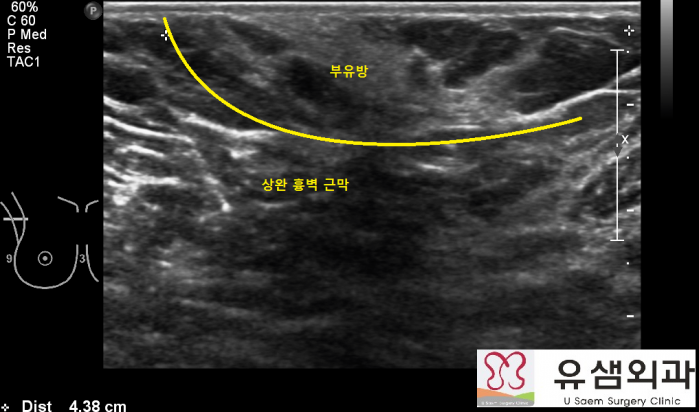

¼ö¼ú Àü ºÎÀ¯¹æÀÇ À§Ä¡¿Í °Üµå¶ûÀÌ µ¿Á¤¸ÆÀÇ À§Ä¡¸¦ ÃÊÀ½ÆÄ¸¦ ÀÌ¿ëÇÏ¿© ÆÄ¾ÇÇÑ ÈÄ ¸¶Å·

ÆæÀ¸·Î Ç¥½ÃÇÕ´Ï´Ù. ±× ÈÄ ºÎÀ¯¹æ À§¿¡ Àû´çÇÑ Å©±âÀÇ Àý°³Ã¢À» Ç¥½ÃÇÕ´Ï´Ù.

¼ö¼ú Áß ÃÊÀ½ÆÄ·Î ºÎÀ¯¹æÀÇ ¹üÀ§¸¦ ÆÄ¾ÇÇÑ ÈÄ¿¡ »ó¿Ï È亮 ±Ù¸·À» È®ÀÎÇϰí, ±Ù

¸· ÁÖº¯°ú ºÎÀ¯¹æÀÇ Áö¹æ ºÎºÐ¿¡ ±¹¼Ò¸¶ÃëÁ¦(Æ©¸Þ½¼Æ®¿ë¾×À» »ç¿ëÇÏ¿© ¾ÆÁÖ Å«

ºÎÀ¯¹æµµ ±¹¼Ò¸¶Ãë·Î ÀýÁ¦ÇÒ ¼ö ÀÖ½À´Ï´Ù.)¸¦ ÁÖ»çÇÕ´Ï´Ù.

¼ö¼ú Áß »ó¿Ï È亮 ±Ù¸·ÀÌ ºÎÀ¯¹æÀÇ ¾Æ·§ÂÊ °æ°è¸¦ ³ªÅ¸³»±â ¶§¹®¿¡ ±Ù¸·À» Àý

°³ÇÏÁö ¾Ê°í ºÎÀ¯¹æÀ» ÀýÁ¦ÇÏ´Â °ÍÀÌ Áß¿äÇÕ´Ï´Ù. ¸¸¾à ±Ù¸·À» Àý°³ÇÏ°í ±× ¾Æ